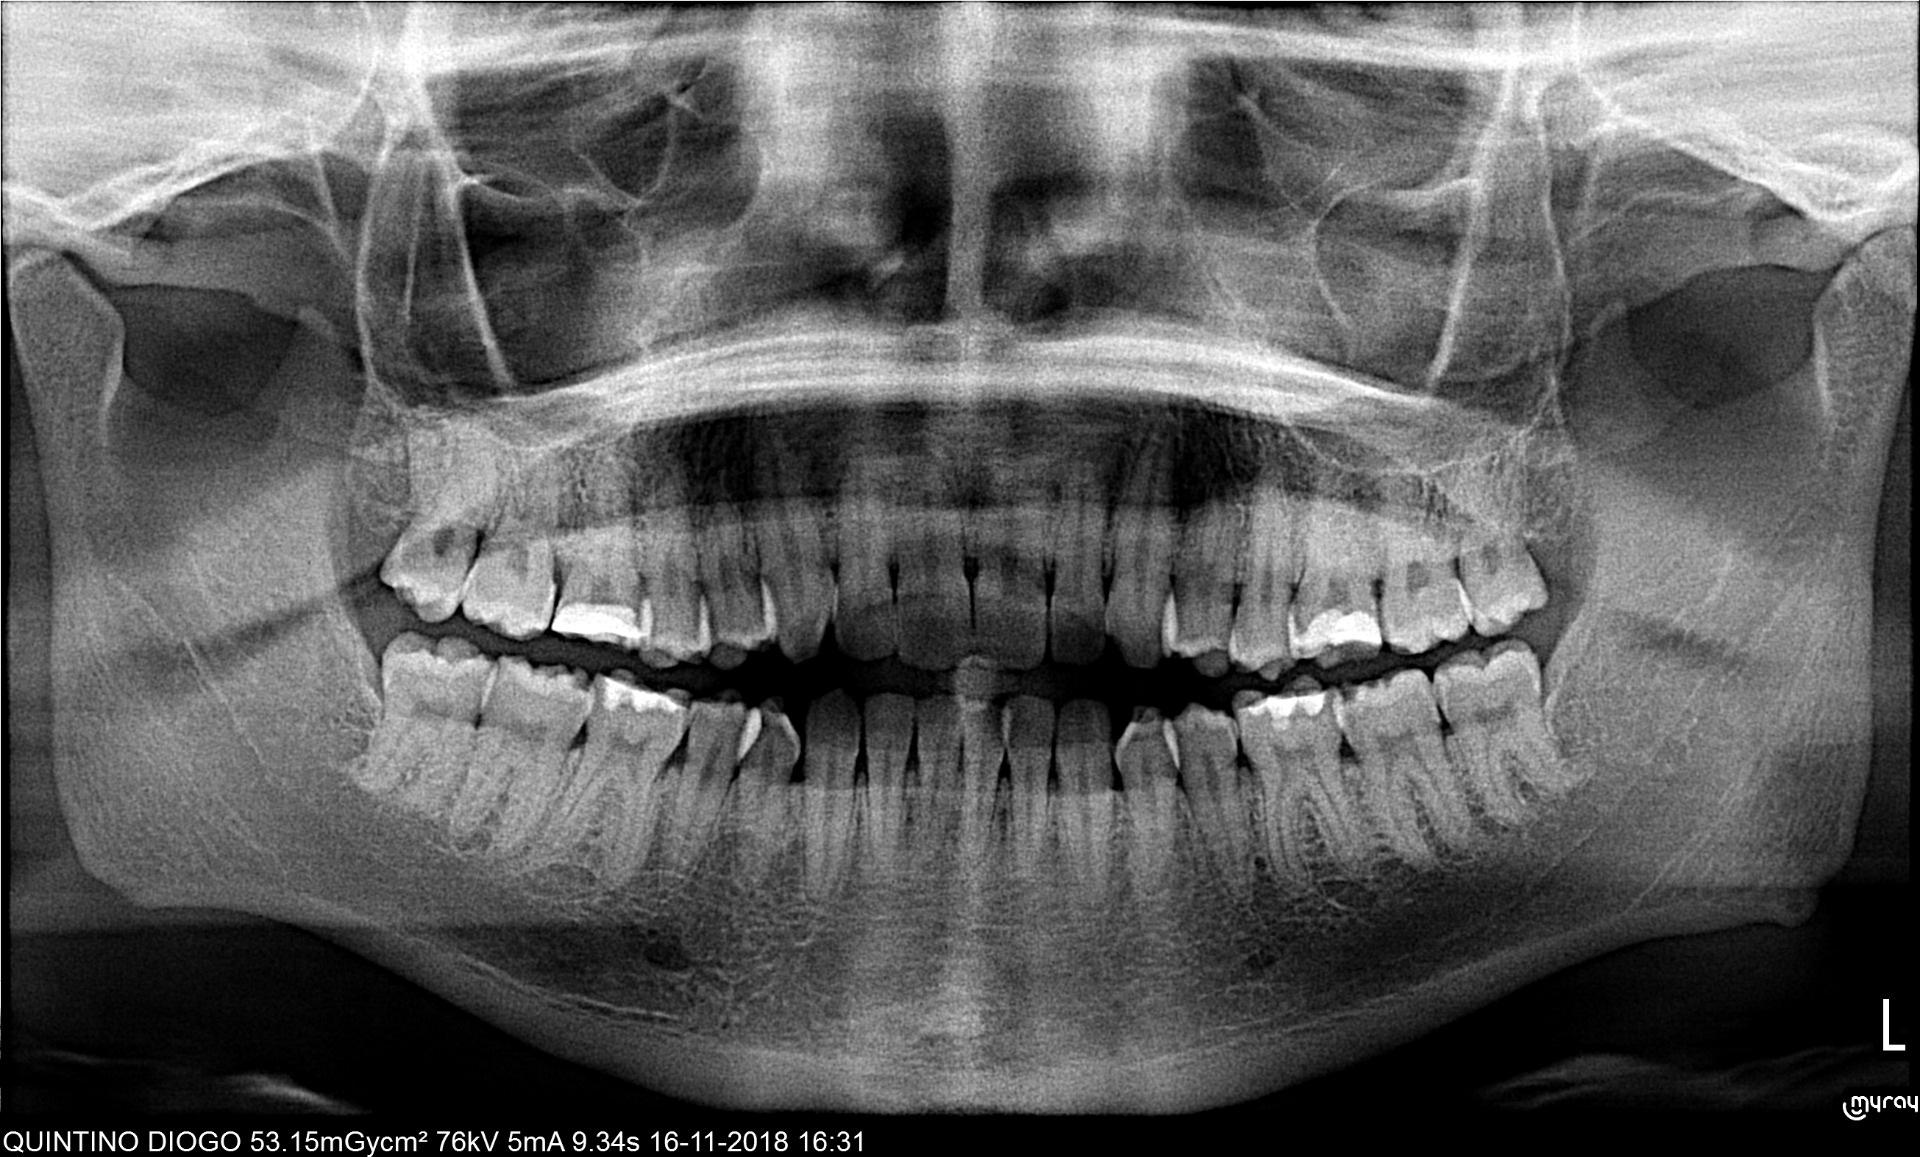

A ortopantomografia, também designada de radiografia panorâmica, é um exame radiológico que serve como meio auxiliar de diagnóstico. São obtidas imagens do maxilar superior e inferior, tornando possível visualizar tanto todas as peças dentárias como algumas estruturas anatómicas adjacentes, os seios maxilares, articulações (ATM).

O ortopantomógrafo usa uma pequena dose de radiação para capturar imagens radiográficas da boca completa apenas numa única imagem, podendo ser efectuada tanto no adulto como na criança